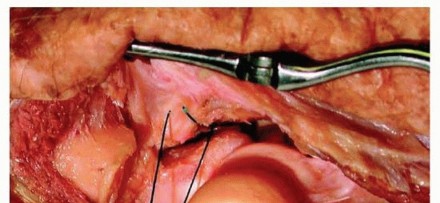

Step 5 & 6: Address Residual Instability. If the elbow demonstrates residual valgus instability or posterior subluxation during the functional arc, the surgeon must proceed to Step 5: exploration and repair of the MCL via a medial approach. If, after MCL repair, the joint remains unstable (a rare occurrence if the osseous anatomy was correctly restored), Step 6 is invoked: the application of a dynamic hinged external fixator. This highly specialized device maintains concentric reduction while allowing for early, protected motion, neutralizing deleterious shear forces during the critical early phases of ligamentous healing.